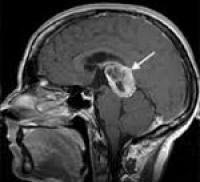

Mai mult, un pas important de diagnostic va fi de a efectua o tomografie computerizată și rezonanța magnetică a creierului. În această etapă, este posibil să se stabilească dimensiunea tumorii, localizarea și natura germinoamele.